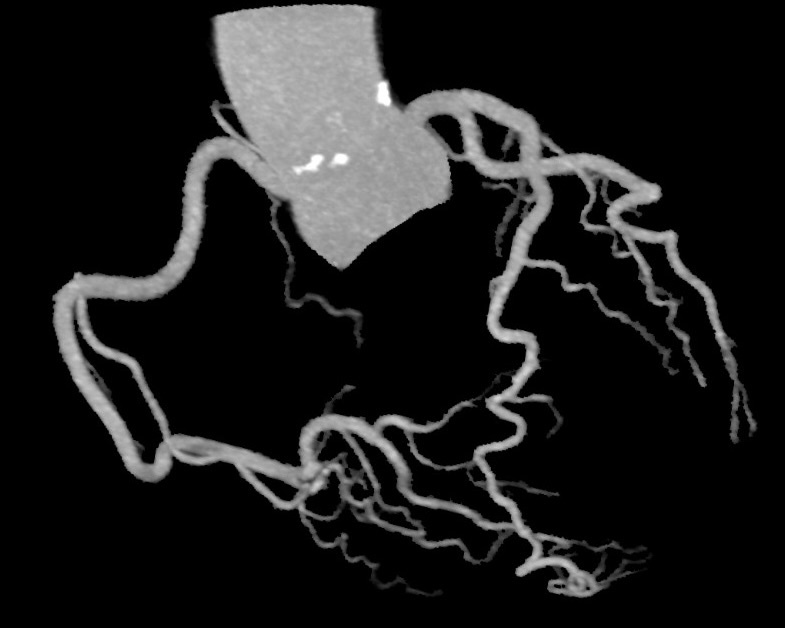

冠動脈CT

造影剤を用いて撮影することにより、心臓を栄養している動脈(冠動脈)の狭窄や閉塞によって起こる、狭心症の評価や予防に有用です。

MIP表示